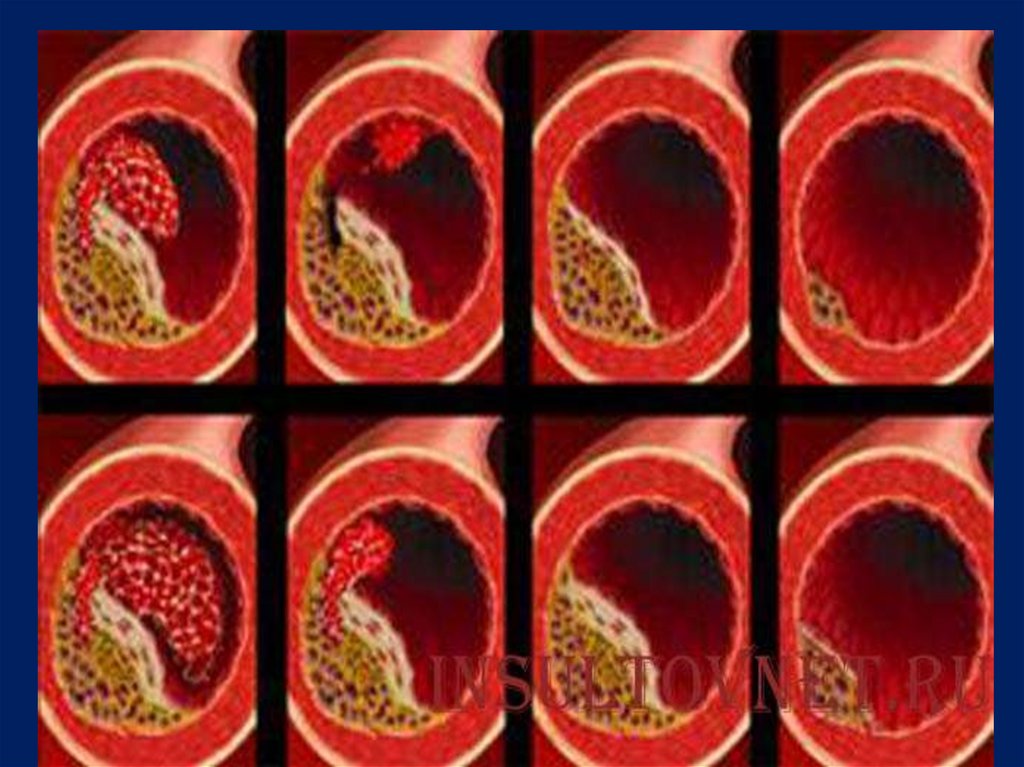

5.

Морфология тромба.

Тромб прикреплен к стенке сосуда в месте

ее повреждения, где начался процесс

тромбообразования. Поверхность его

гофрированная.

Тромб, плотной консистенции, сухой.

6. В зависимости от строения и внешнего вида:

1.

Белый тромб состоит

из тромбоцитов,

фибрина и лейкоцитов

( в артериях).

7.

2. Красный тромб,

помимо тромбоцитов

и фибрина, содержит

большое число

эритроцитов (в венах).

8.

3. Смешанный тромб

имеет слоистое

строение (слоистый

тромб) и пестрый вид,

содержит элементы как

белого, так и красного

тромба (в венах, в

полости сердца).

9.

В смешанном тромбе

различают:

головку (белый тромб), тело

(смешанный тромб) и хвост

(красный тромб)